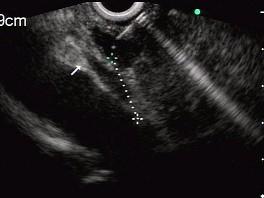

问题 男性,50岁,上腹隐痛,食欲不振3个月。1个月来出现黄疸且进行性加深,体重明显减轻,查体全身明显黄染,肝未触及,深吸气时可触到肿大胆囊底部,无触痛。化验血胆红素15mg/dl,尿检胆红素阳性图中胰腺病变可能的诊断是 ( )

选项 A、胰腺囊腺癌 B、胰腺癌 C、胰腺囊肿 D、慢性胰腺炎 E、正常

答案 B